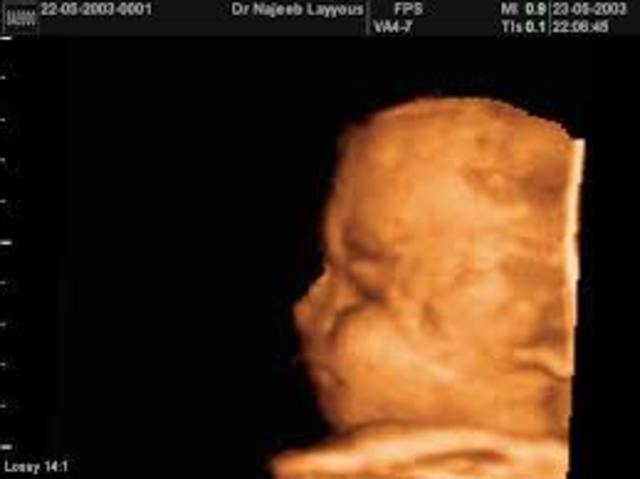

The fetus is very active. Some of the activities include stretching, kicking, sucking the thumb, and opening and closing the eyes. The fetus can hear sounds.